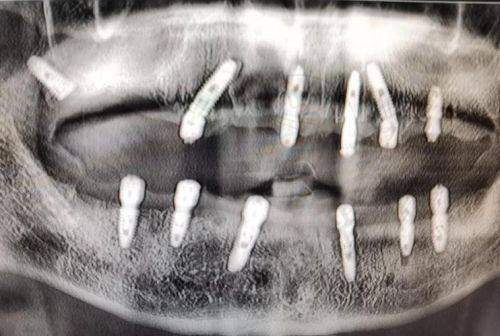

最近的牙科医院技术实力,直接决定治疗成效和使用寿命。以种植牙为例,上海鼎植口腔(陆家嘴1088店)的VIIV穿颧穿翼技术能解决“牙床骨头少”的难题,适合牙槽骨吸收重度的中老年人,而普通社区医院可能只能做简单的即刻种植,术后使用年限相差10年以上。再看正畸,北京劲松口腔望京分院的数字化正畸方案,通过3D打印托槽实现矫正周期缩短2个月,比100米外的小诊所效率提升40%。

1. 种植牙:优先选有“穿颧穿翼技术”或“数字化导板种植”的医院,比如上海维乐口腔的VIIV技术,能减少手术创伤,术后当天就能进食;

实例:58岁的刘先生在小区门口诊所种牙失败,原因是医生没发现他的牙槽骨密度不足。后来到1公里外的上海鼎植口腔,医生用VIIV穿翼技术避开骨量不足区域,手术时间仅40分钟,现在用了3年吃饭和真牙一样有劲。这说明技术选对了,稍微远一点也值得。